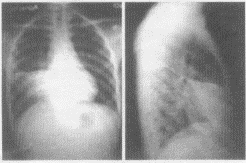

2.患者行胸片正侧位检查,胸片图像表现如下,你认为该患者应首先考虑哪些疾病

D.右中下肺野形成一片密度增高的阴影,与右心缘相连,其上缘锐利平直,由此向下逐渐变淡,移行至正常透亮的肺野,肋膈角清晰

E.侧位片上呈三角形,尖端指向肺门,底部紧接前胸壁或肋膈角,上缘以横裂为界,下缘为斜裂的前半部